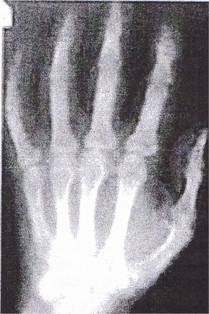

Le document ci-dessous correspond à la radiographie d’une main. La main placée contre la plaque sensible s’intercale entre la source de rayons X et la plaque.

En raisonnant sur les os et les tissus de la main, répondre aux questions suivantes :

2.1 Quelle partie de la main a absorbé le plus de rayons X ? Justifier la réponse.

2.2 Connaissant les éléments chimiques présents dans les os et les tissus, donner une explication possible justifiant la différence d’absorption qui apparaît sur la radiographie.

2.1 La partie des os a plus absorbé les

rayons X : ils n’ont pas impressionné le film photographique puisque la

partie des os apparait en blanc.

2.2 Le calcium et le phosphore ont des numéros atomiques, Z, plus élevés que ceux des autres atomes présents: ils absorbent mieux les rayons X.